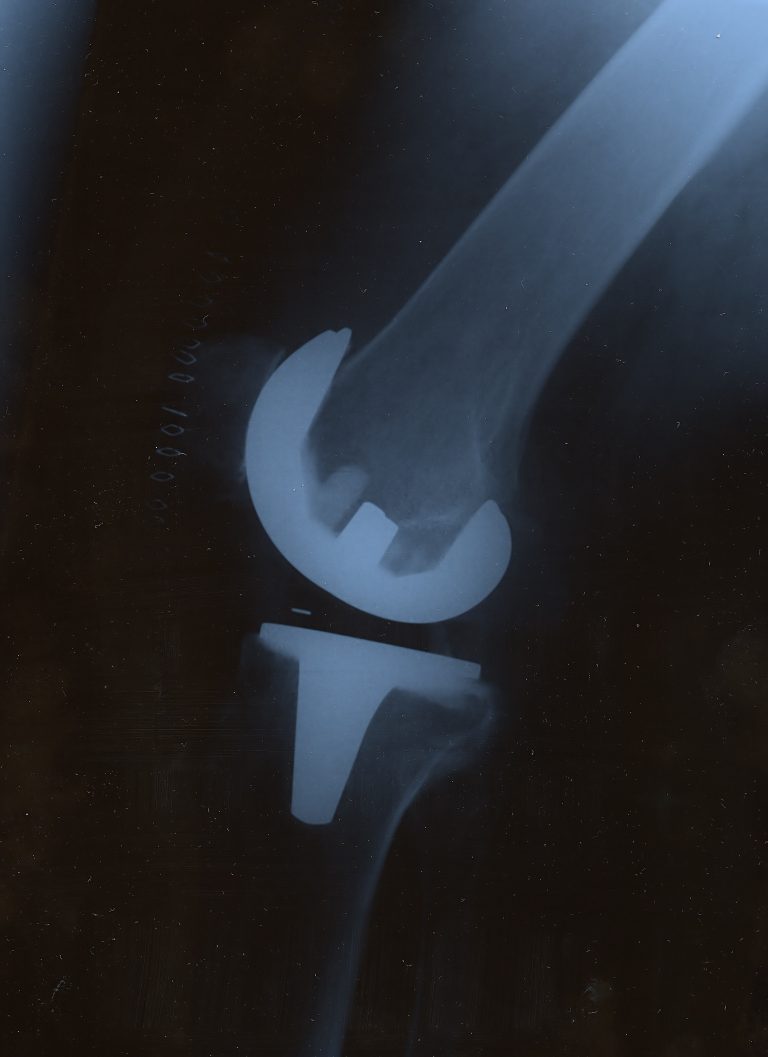

Xray of artificial knee joint Stock Image C002/6461 Science What Is An Artificial Knee a total knee replacement (tkr) is a complex procedure that requires an orthopedic surgeon to make precise measurements and. what is an artificial knee? knee replacement, also called knee arthroplasty or total knee replacement, is a surgical procedure to resurface a knee. for most people, knee replacement provides pain relief, improved mobility and a better quality. What Is An Artificial Knee.